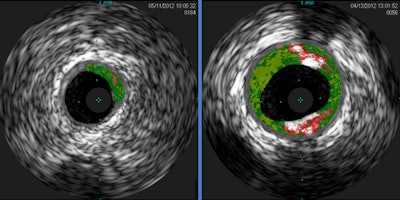

The investigators analyzed blood samples from 118 adults and found antibodies to alpha-Gal in 26%. Next, they used intravascular ultrasound (IVUS) to analyze the quantity of plaque in the blood samples. The amount was 30% higher in the alpha-Gal-sensitized patients than in the nonsensitized patients.